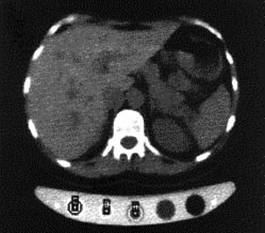

Tomografia computerizata cantitativa (QCT - Quantitative Computed Tomography) permite sectionarea osului de catre computer si selectarea regiunii ce prezinta interes (ROI's - regions of interest), in timp ce se determina densitatea (figura 20). Prevede masurarea densitatii volumetrice reale (stiindu-se aria regiunii de interes si grosimea bucatii). Se foloseste "fantoma" densitatii stiute pentru a calibra imaginea in nuante de gri. Masurile caracteristice se fac in sira spinarii sau in sold. Metoda implica o anumita doza de radiatii si se utilizeaza pentru a se distinge pacientii normali de cei osteoporotici.

Figura 20 Imaginea sirei spinarii prin QCT